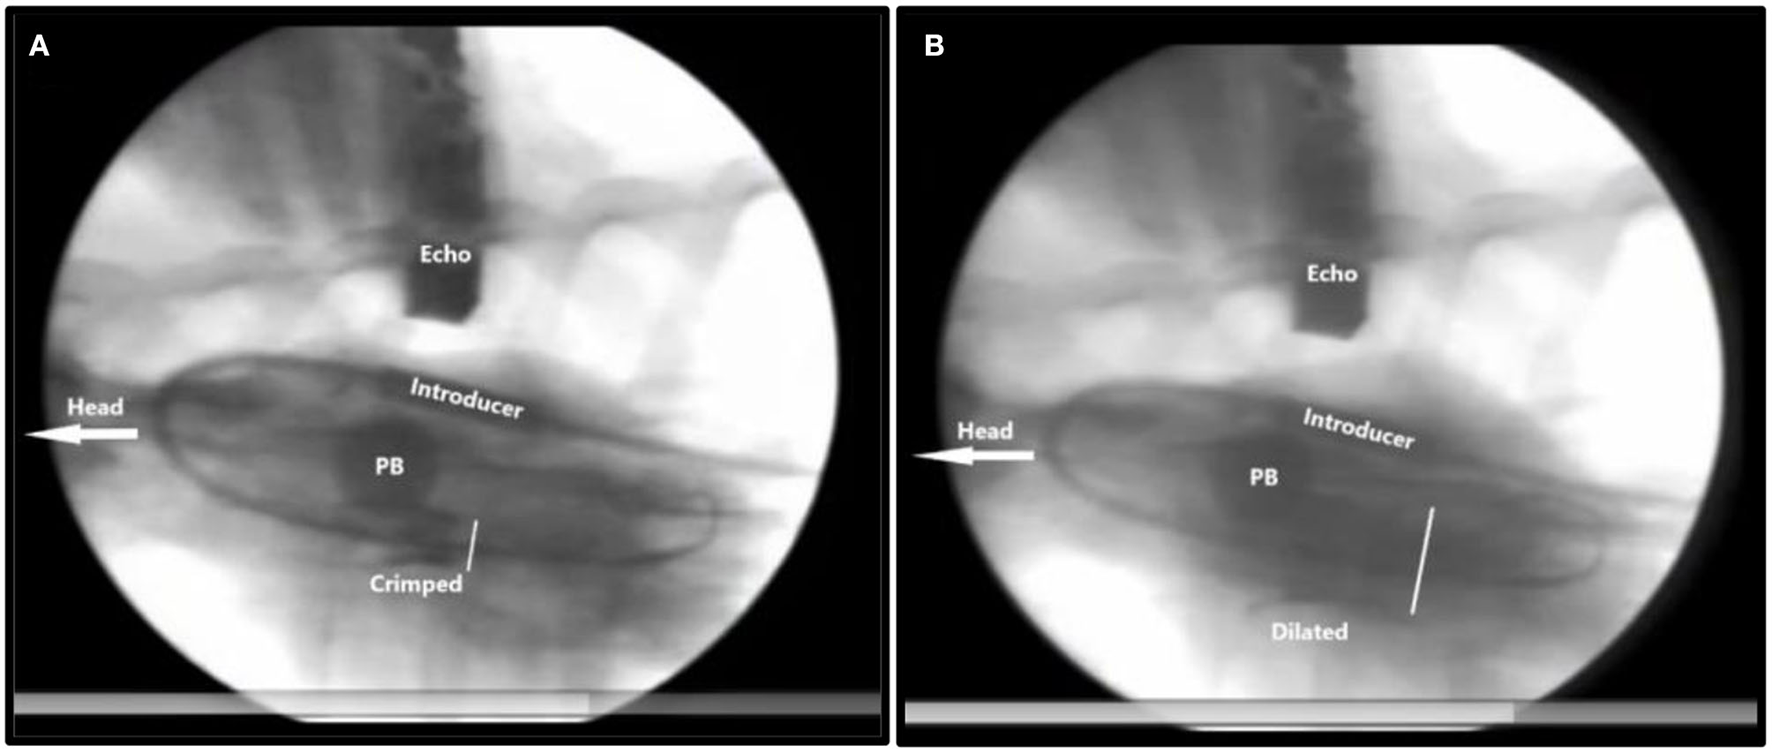

Figure 6

X-ray of TAVI implantation in a pig. The head of the animal is to the left. Inflated pulmonary balloon (PB) occluding the pulmonary artery trunk stopping blood flow toward the lungs and the heart. (A) Crimped = The crimped TAVI valve in the aortic annulus. (B) Dilated = The balloon dilated TAVI valve. The white bar measures the diameter of the TAVI valve. Introducer = the 41Fr. introducer sheath. Echo = transthoracic echo transducer.